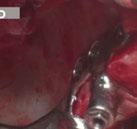

Se obtuvieron modelos de estudio (Figuras 3-6) digitales mediante un escáner confocal de luz azul estructurada (PrimeScan, Dentsply Sirona) y se planificó un protocolo de desgaste mínimamente necesario y conservador de las estructuras

Figura 1. Caso inicial. Figura 2. Vista oclusal superior.

dentarias, cumpliendo parámetros biológicos, terapéuticos, mecánicos y estéticos. Después se realizó un modelado digital retrospectivo (Figuras 7-11) para generar modelos impresos 3D para realizar el mock up funcional, estético y como guía para las preparaciones (Figuras 12-15). Con ello, se efectuaron las preparaciones dentarias y los registros intermaxilares y, posteriormente, se digitalizaron ambos maxilares (Figuras 16-21)